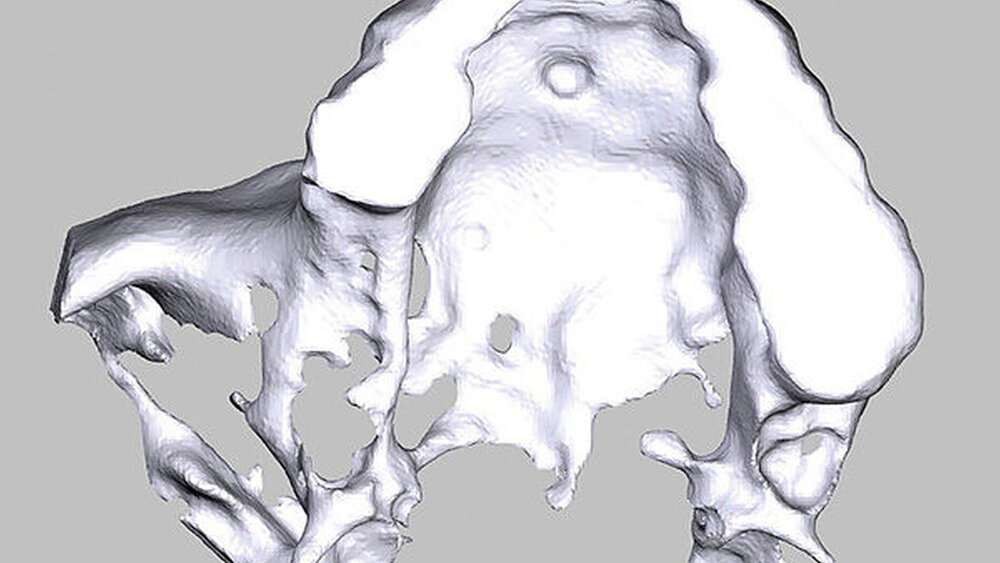

Aufgrund einer ausgeprägten Alveolarkammatrophie im Bereich des rechten Oberkiefers wurde uns eine 62-jährige Patientin zur Augmentation und Implantation überwiesen. Sie hatte ein Implantat regio 16 aufgrund einer Periimplantitis verloren, der Zahn 14 war kurze Zeit vorher extrahiert worden, der Kieferkamm regio 15 war schon lange Jahre zahnlos. Nach wie vor kam für die Patientin nur festsitzender Zahnersatz infrage. Zahn 18 war zwar noch in situ, für eine Brückenversorgung war die Schaltlückenspanne von Zahn 13 auf Zahn 18 aber deutlich zu groß. Nach eingehender klinischer und radiologischer Untersuchung, ausführlicher Besprechung aller Alternativen und einer eingehenden Risikoaufklärung entschied sich die Patientin für die Alveolarkammrekonstruktion mittels CAD/CAM-gefertigtem individualisierten allogenen Knochenblocks. Die DICOM-Daten des angefertigten Oberkiefer-DVTs wurden an die botiss biomaterials GmbH übermittelt. Dort wurde der allogene Spenderblock digital designt, virtuell wurden Implantate aufgestellt und die Planung wurde zur Korrektur zurück an unsere Praxis gesendet. Nach Freigabe durch den Operateur konnte mit der Fertigung des allogenen Blocks begonnen werden.

Die Schnittführung wurde nach dem Pillar-Sockel-Design (Blume) vorgenommen. Dabei liegt die Inzision weit im Vestibulum und verbindet zwei vertikale Entlastungsschnitte. Im Gegensatz zu der herkömmlichen krestalen Schnittführung bleibt das Periost über dem augmentierten Bereich damit völlig intakt. Nach der streng subperiostalen Präparation erfolgte die Kontrolle der Passung des CAD/CAM-Blocks. Ein ganz entscheidender Punkt ist, vor jeglichem Kontakt des Blockes mit Blut diesen in steriler Kochsalzlösung und am besten in der PRF-Flüssigkeit zu wässern, sodass sich keine Poren des Blocks mit Blutkoageln verschließen und innerhalb des Blocks ein nicht mit Blut gefüllter Hohlraum bildet. Vor der Befestigung des Blocks wurde die Kompakta des Empfängerbetts mit einer kleinen Kugelfräse mehrfach perforiert um sogenannte Bleeding Points zu setzen, die die Durchblutung des Knochenblocks gewährleisten. Mit zwei Osteosyntheseschrauben mit dem Durchmesser 1,5 mm und der Länge 9 mm wurde der allogene Knochenblock rotationssicher fixiert. Das Augmentat wurde mit einer dünnen Schweinepericard-Membran (Jason membrane, botiss biomaterials GmbH, Vertrieb Straumann) und der PRF-Membran abgedeckt. Der spannungsfreie Wundverschluss erfolgte mit der modifizierten vertikalen Matratzennaht nach Laurrell mit resorbierbarem Nahtmaterial (Vicryl 4.0). Postoperativ wurde ein Oberkiefer-DVT angefertigt. Die Nahtentfernung wurde im Rahmen der Nachsorgeuntersuchung sieben und 14 Tage postoperativ vorgenommen. Nach einer Heilzeit von sechs Monaten erfolgte die Implantation in Lokalanästhesie unter antibiotischer Abschirmung mit 2 g Amoxicillin oral eine Stunde präoperativ. Die Schnittführung erfolgte krestal, und nach subperiostaler Präparation wurde der Knochenblock dargestellt und die Osteosyntheseschrauben wurden entfernt. Danach wurden drei Implantate (Straumann) in den Knochenblock gesetzt und mit 0er-Verschlussschrauben abgedeckt. Die Wundrandadaptation erfolgte mit resorbierbarem Nahtmaterial, das bei der Verlaufskontrolle sieben Tage postoperativ vollständig entfernt wurde. Nach dreimonatiger gedeckter Einheilung wurden die Implantate im Rahmen einer Vestibulumplastik freigelegt. Dafür wurde eine erneute krestale Schnittführung regio 14 bis 17 vorgenommen und ein Splitflap präpariert. Der vestibuläre Wundrand wurde mit Einzelknopfnähten im Vestibulum fixiert. Im Bereich der Implantate wurde der Splitflap perforiert, um die Abdeckschrauben gegen Gingivaformer auszutauschen, und der Bereich des nun freiliegenden Bindegewebes wurde mit einer 3D-vernetzten Kollagenmatrix (mucoderm, botiss biomaterials GmbH, Vertrieb Straumann) abgedeckt. Diese wurde zunächst gewässert, um die Verarbeitung zu erleichtern, und an den Stellen der Gingivaformer gestanzt. Die Nahtentfernung erfolgte neun Tage postoperativ. (Abb. 1a bis 1f).